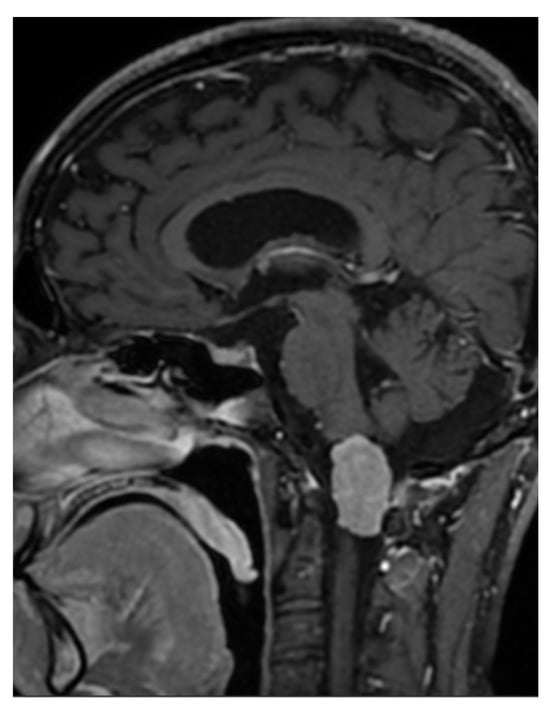

Case Report